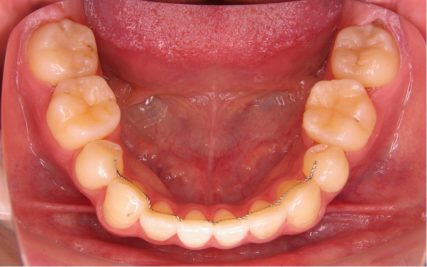

でこぼこ/20代女性

- 不正咬合/叢生(でこぼこ)

- 上下とも前歯のスペース不足が認められた。歯のサイズと顎の幅とのバランスが不調和な事が原因の1つとして考えられる。

- 上顎両側4番・上顎両側8番・下顎両側4番・下顎両側8番抜歯

- マルチブラケット装置(セルフライゲーションブラケット)/歯科矯正用アンカースクリュー

- 前歯部のでこぼこが解消され、正常咬合を獲得する事が出来た。又、歯科矯正用アンカースクリューを用いる事で抜歯スペースを有効に利用できた。